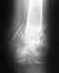

Добрый день! Я подвернул ногу, в больницу сделали снимок, поставили диагноз- перелом лодыжки.

• Кликните для загрузки файла перелом1.JPG